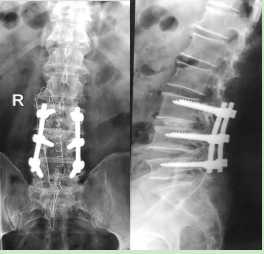

3.腰椎椎管狹窄行腰椎椎間盤切除椎間植骨融合內(nèi)固定術(shù)后